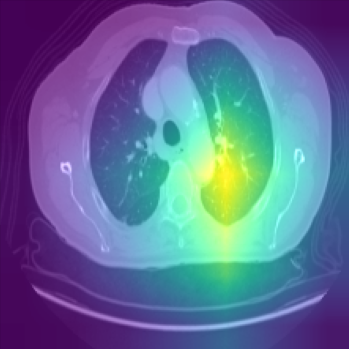

Class activation heat-map development

The final step involves the generation of feature visualisation heat-maps, elucidating the decision-making process of the trained model, and assessing its reliability. Feature visualisation is valuable for uncovering and understanding the learnt features within DL models. Zhou et al. (2016) introduced the Class Activation Mapping (CAM) method, which incorporates a global average pooling layer into a standard CNN. This innovation facilitated the identification of critical feature contributions linked to CNN’s specific predictions, shedding light on the rationale behind the model’s decisions. Furthermore, Selvaraju et al. (2017) introduced Gradient Weighted Class Activation Mapping (Grad-CAM), using gradients from the network’s final convolutional layer to generate a coarse localisation map. This map highlights influential regions within an image that contribute to the prediction of specific concepts or classes. In our study, we embraced the Grad-CAM technique on the model’s final layer to generate class-specific heat-maps. The objective is to unveil evidence of how the models arrive at predictions, with the heat-maps delineating regions of significance in the model’s prediction rationale.

Comparison using XAI techniques